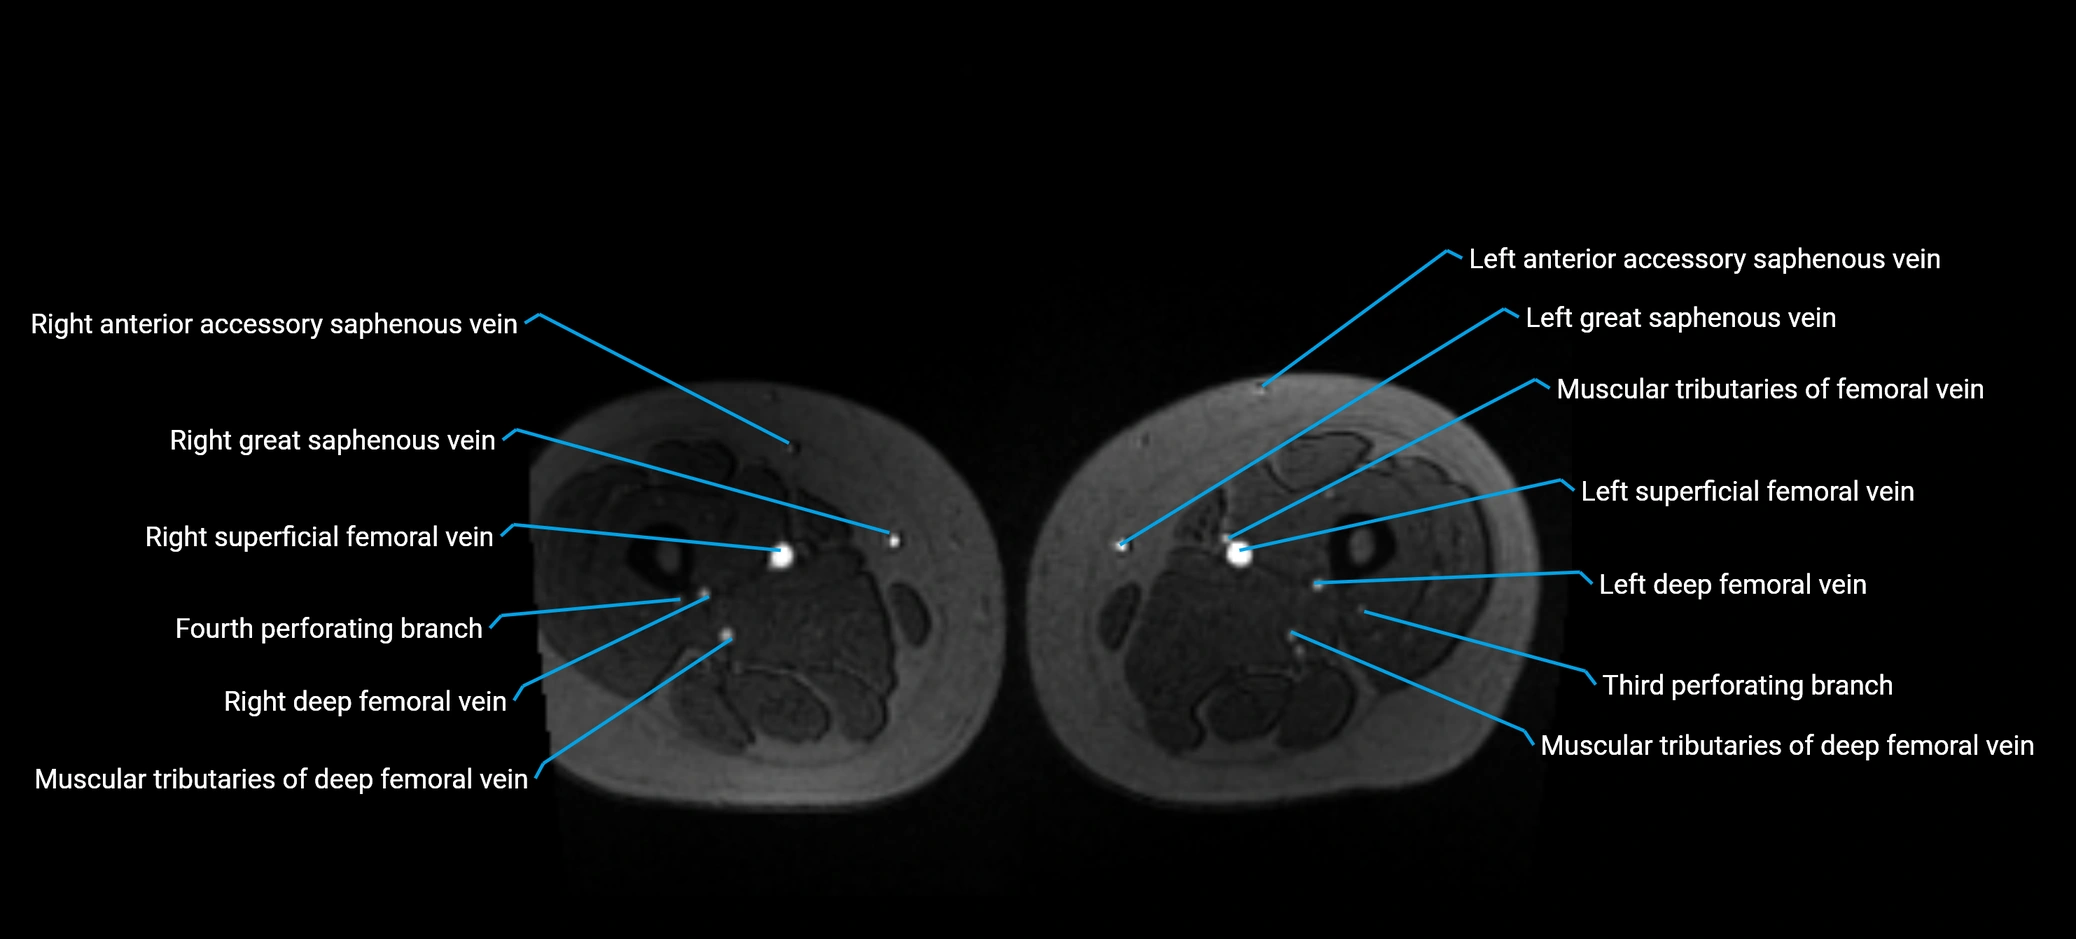

MRI image

image